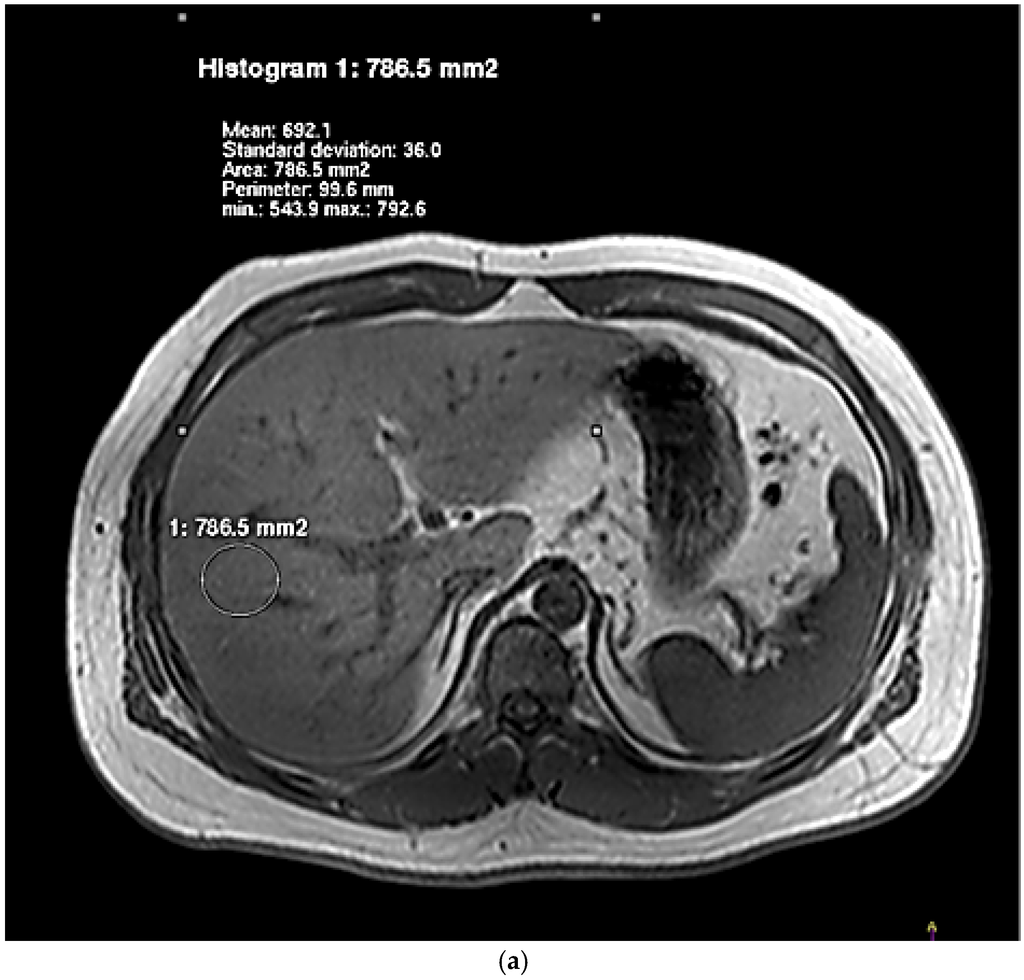

Associations between Dietary Nutrient Intakes and Hepatic Lipid Contents in NAFLD Patients Quantified by 1H-MRS and Dual-Echo MRI

by Yipeng Cheng, Kewei Zhang, Yang Chen, Yanchuan Li, Yuzheng Li, Kuang Fu and Rennan Feng

Nutrients 2016, 8(9), 527; https://doi.org/10.3390/nu8090527 - 27 Aug 2016

Dietary habits are crucial in the progression of hepatic lipid accumulation and nonalcoholic fatty liver disease (NAFLD). However, there are limited studies using 1H-magnetic resonance spectroscopy (1H-MRS) and dual-echo in-phase and out-phase magnetic resonance spectroscopy imaging (dual-echo MRI) to assess [...] Read more.

Dietary habits are crucial in the progression of hepatic lipid accumulation and nonalcoholic fatty liver disease (NAFLD). However, there are limited studies using 1H-magnetic resonance spectroscopy (1H-MRS) and dual-echo in-phase and out-phase magnetic resonance spectroscopy imaging (dual-echo MRI) to assess the effects of dietary nutrient intakes on hepatic lipid contents. In the present study, we recruited 36 female adults (NAFLD:control = 19:17) to receive questionnaires and medical examinations, including dietary intakes, anthropometric and biochemical measurements, and 1H-MRS and dual-echo MRI examinations. NAFLD patients were found to consume diets higher in energy, protein, fat, saturated fatty acid (SFA), and polyunsaturated fatty acid (PUFA). Total energy intake was positively associated with hepatic fat fraction (HFF) and intrahepatic lipid (IHL) after adjustment for age and body-mass index (BMI) (HFF: β = 0.24, p = 0.02; IHL: β = 0.38, p = 0.02). Total fat intake was positively associated with HFF and IHL after adjustment for age, BMI and total energy intake (HFF: β = 0.36, p = 0.03; IHL: β = 0.42, p = 0.01). SFA intake was positively associated with HFF and IHL after adjustments (HFF: β = 0.45, p = 0.003; IHL: β = 1.16, p = 0.03). In conclusion, hepatic fat content was associated with high energy, high fat and high SFA intakes, quantified by 1H-MRS and dual-echo MRI in our population. Our findings are useful to provide dietary targets to prevent the hepatic lipid accumulation and NAFLD. Full article